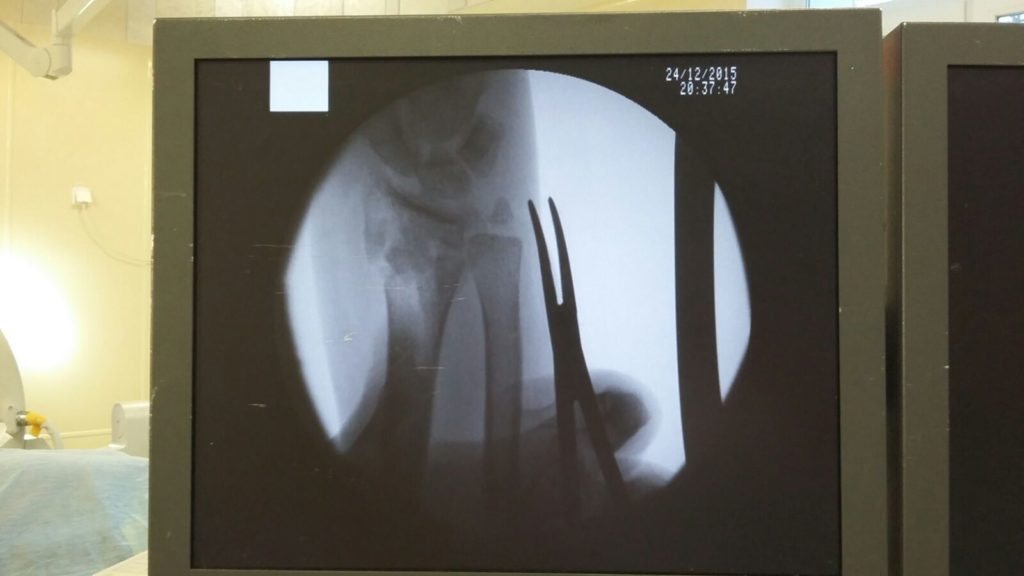

Операция - открытая репозиция, остеосинтез лучевой кости пластиной с костной ксенопластикой материалом "Остеоматрикс". На контрольных снимках в три месяца имеется консолидация перелома, миграции фиксатора нет, имеется остеоинтеграция ксенопластического материала.